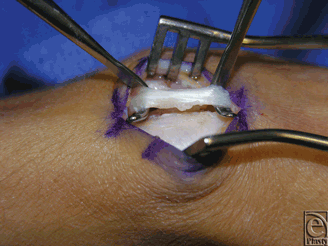

In the operating room, the patient had a ruptured EPL tendon with the proximal end in the mid-forearm and the distal end in the anatomic snuffbox (Fig 1). Repair was performed with an ipsilateral palmaris longus tendon graft. The synovitis noted was resected. There was no obvious bony abnormality or rough edges of Lister's tubercle; however, the third compartment turned at a sharp angle at the distal end of Lister's tubercle (Fig 2).

![]() |

| Figure 1. Intraoperative photograph of patient 2 demonstrating complete rupture of the right EPL tendon with proximal end in visible in the dorsal forearm. EPL indicates extensor pollicis longus. |